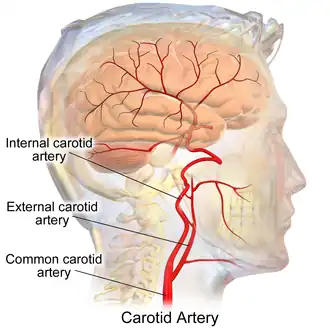

The external carotid artery is the major artery of the head and upper neck. It arises from the common carotid artery. It terminates by splitting into the superficial temporal and maxillary artery within the parotid gland.[1]

Origin

The external carotid artery arises from the common carotid artery just inferior to the upper border of the thyroid cartilage.[1]

At its origin, this artery is closer to the skin and more medial than the internal carotid, and is situated within the carotid triangle.